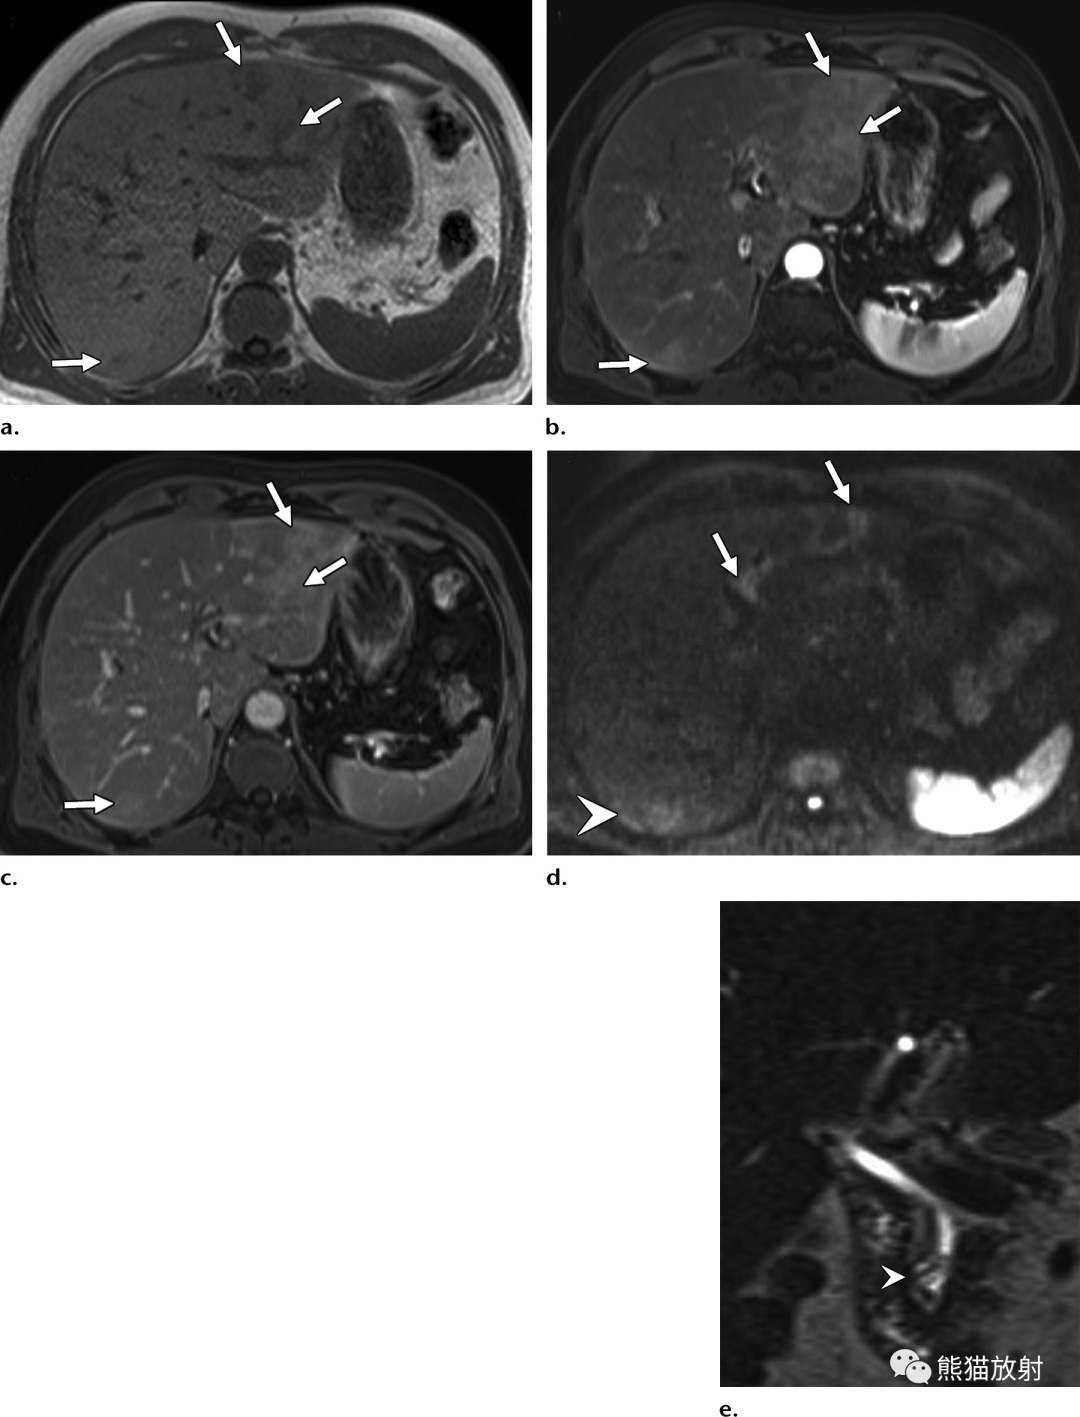

32岁 HIV/AIDS男性患者,细菌性紫癜,表现为发热。

(a)T1WI同相位图像显示肝右叶后段边界不清的等至轻度低信号结节(箭)。(b)脂肪饱和T2WI显示结节呈中高信号(箭),后方肝被膜下见数个较小结节(箭头)。(c)增强动脉早期图像显示结节周围不规则明显强化。(d)增强延迟期结节内部延迟强化,由于造影剂滞留在病灶内扩张的肝窦内,因此达到与周围肝静脉结构相似的信号强度。

60岁男性,肝片吸虫病,入院前3个月出现发热、盗汗,有西洋菜摄入史。(a)T1WI图像显示肝左外叶和肝右后叶包膜下区域内存在边界不清的小片状低信号(箭)。(b)对比增强动脉期脂肪抑制T1WI显示带状分布的炎症(箭)和周围肝实质的早期强化。(c)增强延迟期图像显示造影剂滞留在寄生的带状肝实质中(箭)。(d)扩散加权图像 (b=800s/mm2) 显示肝包膜下不规则管道样、片状扩散受限区,向肝门中心走行(箭)。(e)冠状T2WI显示胆管远端(箭头)不规则线样低信号充盈缺损,内镜检查结果证实为活的寄生虫。